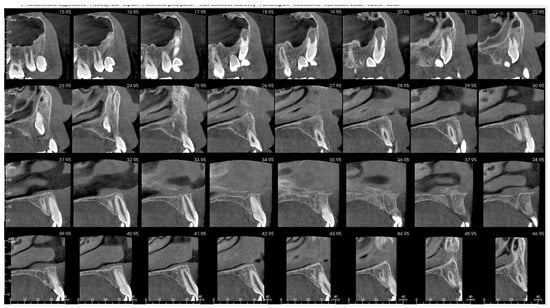

That finding necessitated further diagnostics with CBCT (Figure 4, Figure 5, Figure 6 and Figure 7). A 3D radiograph confirmed a round, well-demarcated, noninflammatory cyst-like lesion extending from Teeth 11 to 15.

CBCT before treatment—axial view.

Figure 6.

A hypodense focus representing a loss of osseous tissue surrounded the crown of the displaced upper right permanent canine. The unerupted first and second premolars were dislocated and rotated, and Tooth 12 also presented mesiorotation and mesioinclination. The teeth involved in the lesion had open apices and no sign of root resorption. The alveolar bone was deformed, especially in the vestibulopalatal dimension, with a noticeable displacement of the medial interior wall of the right maxillary sinus.